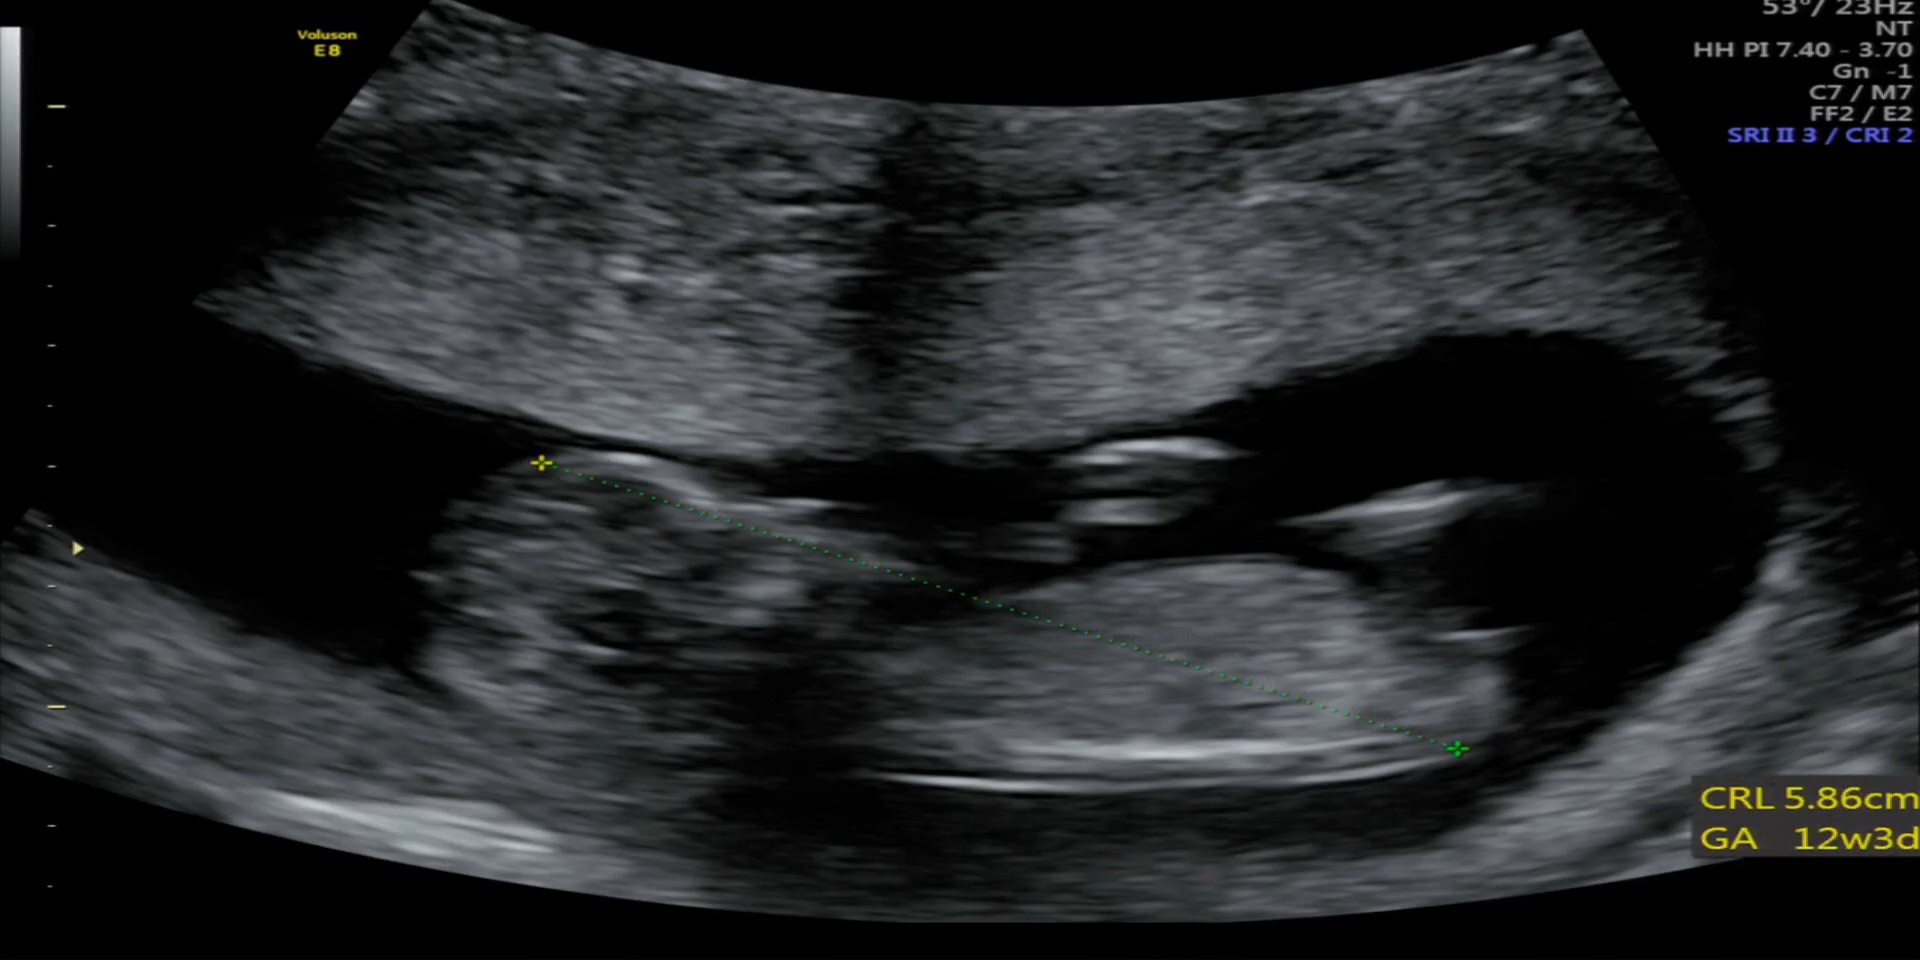

12주 각도법 한번봐주세용